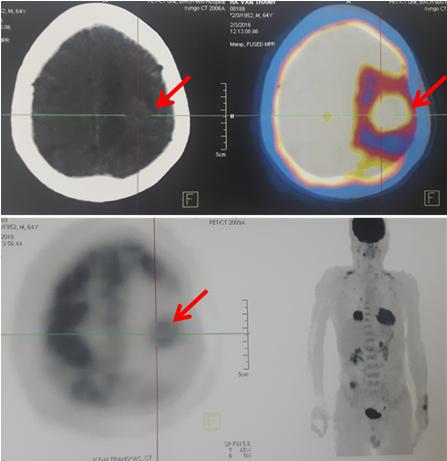

Hình 3: Hình ảnh di căn não trên phim chụp PET/CT

Tổn thương não thùy thái dương đỉnh trái, kích thước 2,1x2,6cm, tăng hấp thu FDG, maxSUV: 8,6; có phù não rộng xung quanh. Không thấy tổn thương tái phát tại đại tràng.